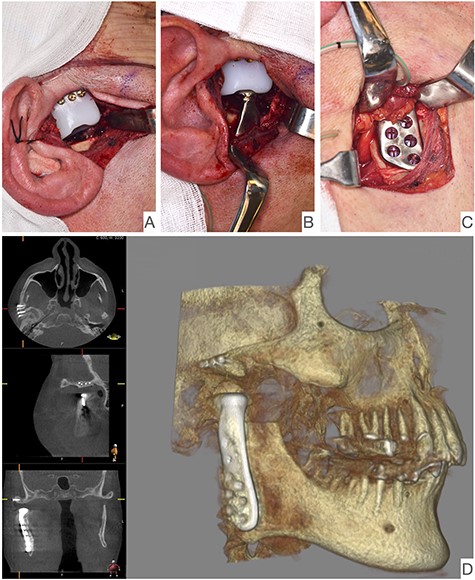

This report is about a 63-year-old patient suffering of bilateral deforming TMJ arthrosis (Wilkes-V) from a bilateral condylar fracture. In 2019 he presented himself to the Department of Oral and Maxillofacial Surgery, showing painful palpation above both TMJs and a severely decreased mouth opening (maximum interincisal distance of 1.5 cm). A computed tomography (CT) scan then revealed pathognomonic changes with flattening of the condyle and articular eminentia as well as partial ankylosis of the right TMJ (Fig. 1). Based on these findings, we decided for a bilateral TMJ-TJR. At this point, the patient only wanted one side replaced for the time being. After impressions were taken, plaster models were 3D-surface scanned and in combination with the CT dataset further processed by Zimmer-BiometTM (Warsaw, USA) for patient-specific TJR (PSI-TJR) fabrication. Another 3 months later, the TMJ-TJR of the right side could be carried out (Fig. 2). Postoperatively the patient received antibiotics for overall 7 days. Satisfied with the result, the patient requested reconstruction of the left TMJ 6 months later. With an improved mouth opening (2.8 cm), impressions were taken using an intraoral scanner. After PSI fabrication, the operation was carried out 9 months after (Fig. 3). Six weeks following surgery, the patient presented with a painful preauricular swelling on the left side, which was diagnosed as aseptic inflammation in the absence of erythema and pathologic joint puncture. Showing a periarticular edema, a broken screw and radial osteolysis around the drilling channels, a subsequent CT scan indicated the loosening of the ultra-high-molecular-weight-polyethylene (UHMWPE) fossa component (Fig. 4). In view of the long production time of new custom-made components and the damaged implant site, we decided to explant the fossa and to temporarily replace it with a non-fixed patient-specific spacer made of COPAL®-bone-cement (Fig. 5) (gentamicin and clindamycin additive) (Haereus; Hanau, Germany). The workflow included the surface scan of the original fossa-drilling template, the computer-aided design of a two-part press mould and the intraoperative fossa fabrication from COPAL®-bone-cement. With the use of a rubber elastic intermaxillary fixation, the vertical mandibular relation could be secured, painful movements and muscle shortening avoided and the risk of perioperative infection could be sufficiently minimized (Fig. 6). After 3 months without complications, the patient-specific COPAL® component could be removed and the new patient-specific UHMWPE fossa inserted within sufficiently regenerated bone (Fig. 7).

Intraoperative image showing the articular fossa (A) in combination with the articulating condylar component (B), the fixed ramus component (C) and the postoperative CBCT of the right side (D).